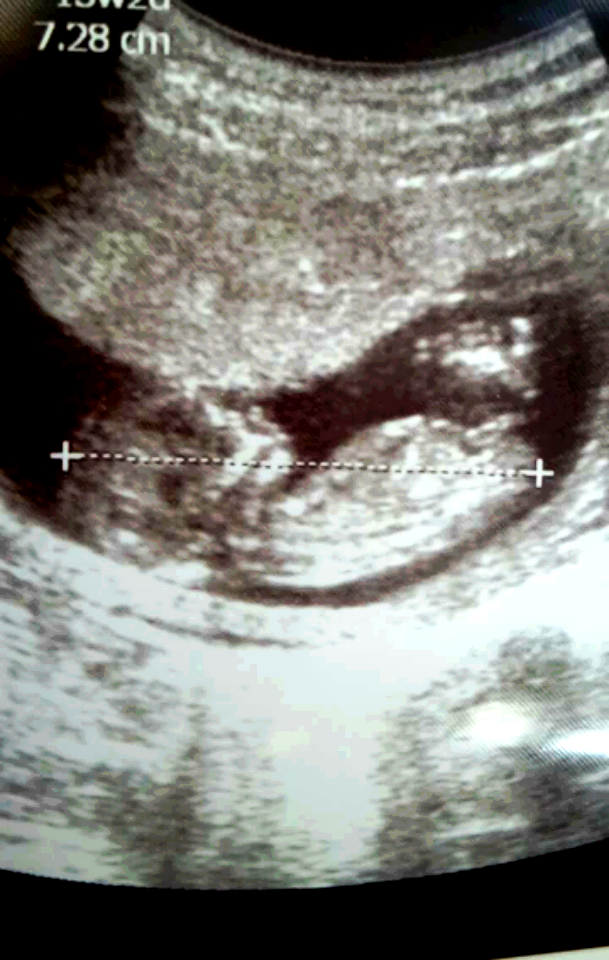

R rma_rma Yeni Üye Üye 7 Ocak 2017 #117 buda benim bebegim 13 haftaligiz .yorum yaparmisiniz rica etsem🙂

Sevimli cadı Daimi Üye Üye 8 Ocak 2017 #120 rma_rma' Alıntı: Ekli dosyayı görüntüle 73270 buda benim bebegim 13 haftaligiz .yorum yaparmisiniz rica etsem🙂 Genişletmek için tıkla ... Sizin bebeğinizin cinsiyeti kız 🙂

rma_rma' Alıntı: Ekli dosyayı görüntüle 73270 buda benim bebegim 13 haftaligiz .yorum yaparmisiniz rica etsem🙂 Genişletmek için tıkla ... Sizin bebeğinizin cinsiyeti kız 🙂